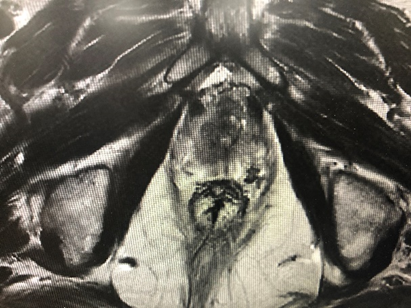

病例四,76岁男性,膀胱肿瘤电切术后2个月,复查CTU提示膀胱癌复发可能,左侧壁不均匀增厚,范围约4cm,尿液TCT+特殊染色提示高级别尿路上皮癌细胞阳性,外院病理切片于本院会诊提示高级别尿路上皮癌(G3),可见广泛固有层侵犯,局灶侵犯固有肌层。行机器人辅助腹腔镜膀胱根治性切除术,盆腔淋巴结清扫术,原位膀胱术,术者:王国良教授。